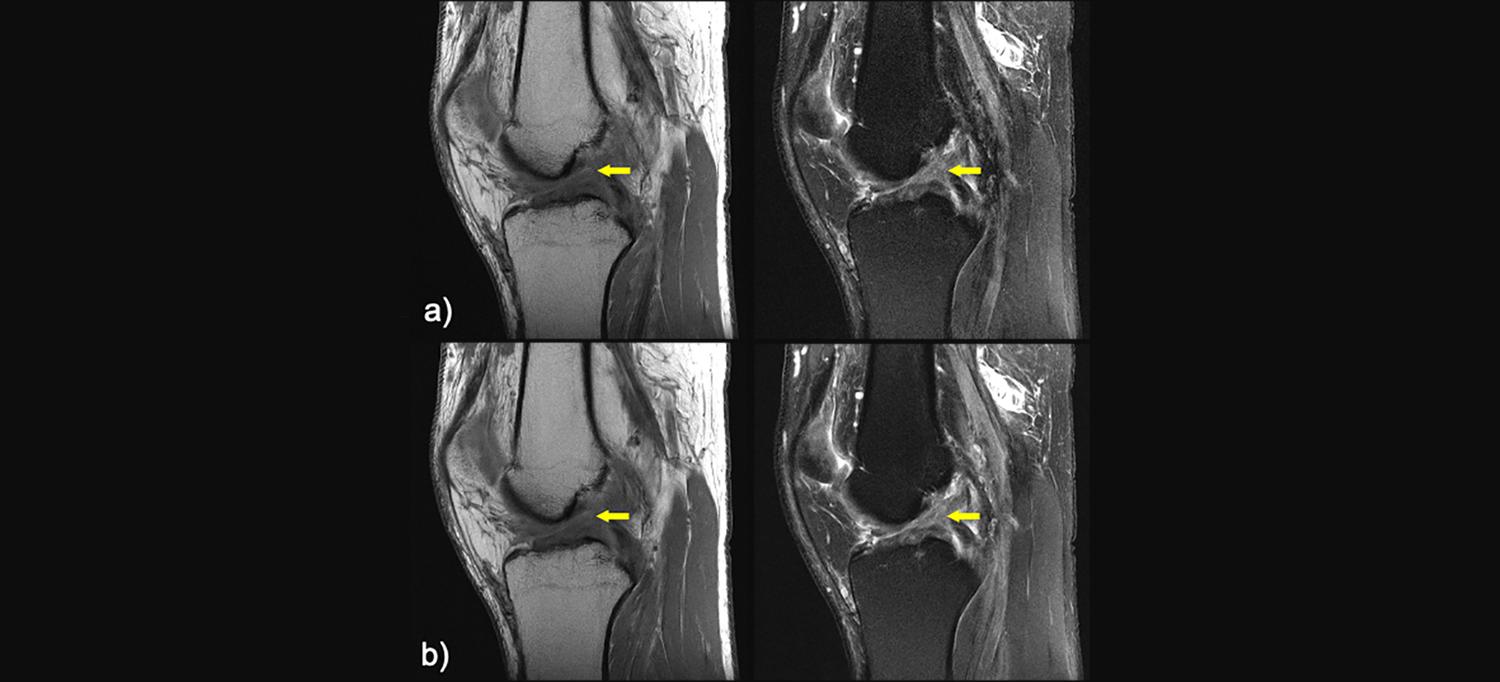

In the new study, a total of 170 participants received a diagnostic knee MRI using a conventional MRI protocol followed by an accelerated AI protocol between January 2020 and February 2021. Each examination was reviewed by six musculoskeletal radiologists, who looked for signs of meniscal or ligament tears and bone marrow or cartilage abnormalities. The radiologists evaluating the scans were not told which images were reconstructed with AI, and to limit the potential for recall bias, the evaluations of the standard images and AI-accelerated images were spaced at least four weeks apart.

The radiologists judged the AI-reconstructed images to be diagnostically equivalent to the conventional images for detecting tears or abnormalities, and found the overall image quality of the accelerated scans to be significantly better than the conventional images.